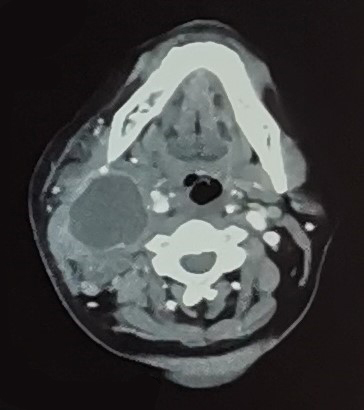

A 43-year-old housewife with no prior medical illness presented with progressive right neck swelling for 3 months' duration, associated with dysphagia and trismus. She reported no history of fever, hoarseness of voice, constitutional symptoms, or contact with pulmonary tuberculosis. Physical examination revealed a large right neck swelling that was tender and fluctuant. CT of the neck and thorax showed a collection within the right carotid space, measuring 1.0×3.1×5.3 cm with resultant anterior displacement of the right submandibular gland, right common carotid artery and internal jugular vein (Figure-1). There were also multiple enlarged and necrotic lymph nodes in the right cervical region. She subsequently underwent incision and drainage of the right neck abscess in which 20 cc of purulent material was drained. Cultures of the purulent material, as well as the intraoperative tissue, grew Morganella morganii, susceptible to cefepime and carbapenems. The histopathological examination findings of the sampled lymph node were negative for both tuberculosis and malignancies. The patient was treated with intravenous cefepime 2 g twice daily for a total of 14 days. The neck swelling reduced in size, and she made a full recovery.